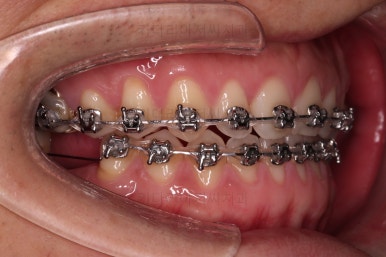

교정장치를 부착하고 충치치료는 별개로 진행되었어요.

이번에 선택하신 장치는 자가결찰(철사를 잡아주는 뚜껑이 자체적으로 달려있는) 메탈(금속)장치이며 엠파워 메탈이라고 하는 장치입니다.

세라믹에 비해 많이 보인다는 단점이 있지만 저렴하고 튼튼한 관리가 약간은 더 편하다는 장점이 있어요.

틈새는 서서히 조여서 없애주고요.

충치치료가 완료된 부위는 골드 크라운(금니)이 씌워졌어요.

임플란트를 하기에 적절한 사이즈로 공간은 맞춰줍니다.

거의 모습이 완성되었습니다.

임플란트는 언제 하게 되나요?

가장 많이 하시는 질문 중 하나인데요. 교정치료가 완료된 뒤에 임플란트를 하면 시간상 효율이 떨어져요.

임플란트는 뿌리 부분부터 머리 부분까지 완성되려면 몇 달의 시간 소요가 있을 수 있기 때문에 교정치료가 완료되기 몇 달 전인 즉, 임플란트 자리만 적절히 마련되면 임플란트를 하게 됩니다.

그 뒤에 임플란트의 완료와 교정치료의 완료가 동시에 되도록 시간세팅을 하면 환자분이 소모하는 시간이 가장 단축되죠.